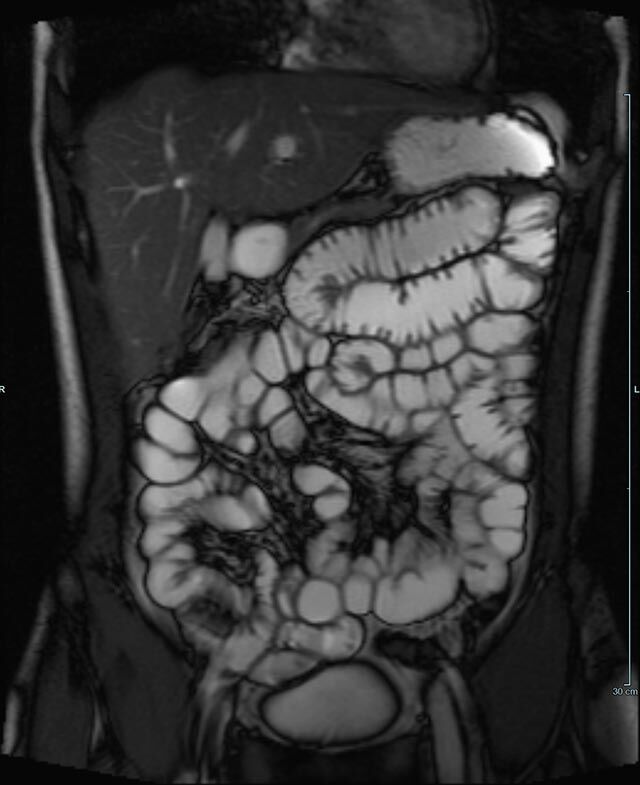

Gelenke

• Beurteilung von Knochen, Bändern und anderen Weichteilstrukturen der Gelenke nach Unfall.

• Arthrosediagnostik (Knorpelschaden)

• Impingement-Symptomatik

• Ursachenklärung bei wiederholter spontaner Gelenkluxation

• Ausbreitungsdiagnostik bei Gelenkentzündung, z.B. im Rahmen von rheumatischen Grunderkrankungen